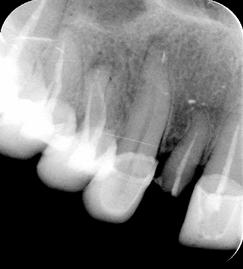

Figura n°1. Caso clínico: Paciente de 46 anos de idade, já portadora de 4 implantes, colocados há 6 anos, compareceu ao consultório após a perda da coroa do dente 12 com fratura da raiz.

Figura n°2. A análise radiográfica, mostrou uma raiz com muito pouca implantação, reação apical e ao exame clínico uma provável linha de fratura, transversal, alterando o ligamento periodontal no terço médio da raiz. Assim a raiz foi condenada, e indicado à paciente um implante imediato. Na radiografia pode-se observar outras alterações nos ápices dos dentes 13 e 14.

Figura n°3. Esta é a fotografia antes da cirurgia para implante. A imagem não ficou boa, mas pode-se notar com atenção uma linha de fratura iniciando na região vestibular com direção à distal.